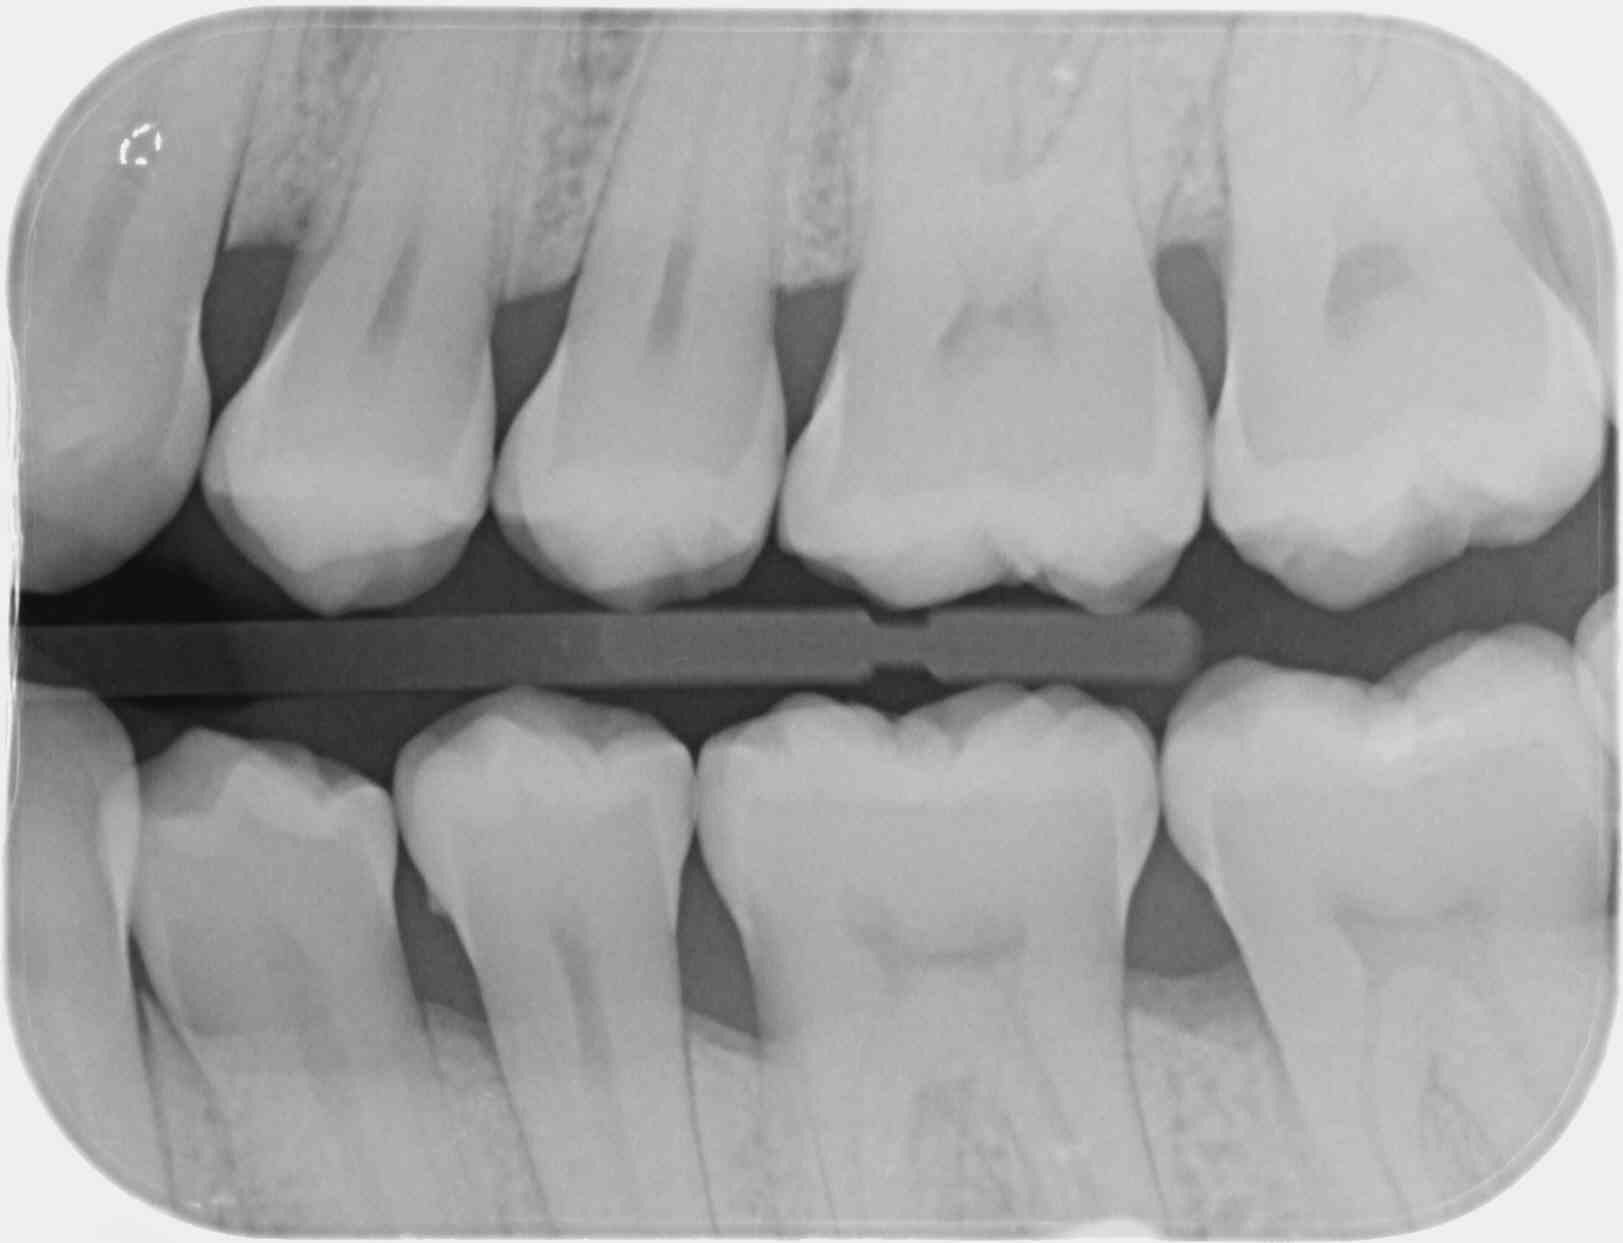

Sur un film 3+ je vois toutes les couronnes de la 7 a la 3... si je fais bite wing gauche et droit ca fait 20 couronnes, je peux compter combien de secteurs ?

T'es con d'utiliser des films taille 3 surtout avec des CDC de bonne composition. ca fait que 2 secteurs ou 4. Alors que 4 clichés ca fait 4 secteurs....ou 8. Les rétro alvéolaires sont offertes. -)

Le problème vois tu avec ces films étendus c'est que moins tu as de clichés moins tu as de dents au centre d'un cliché et moins tu as de secteurs. -)))

Effectivement. C'est pour ça que sur les patients plus âgés je sors le taille 2, qui a l'avantage de permettre l'utilisation du collimateur. Par contre, on ne peut pas avoir en même temps les canines et les DDS. Le taille 1 suffit souvent sur les patients jeunes sans DDS.